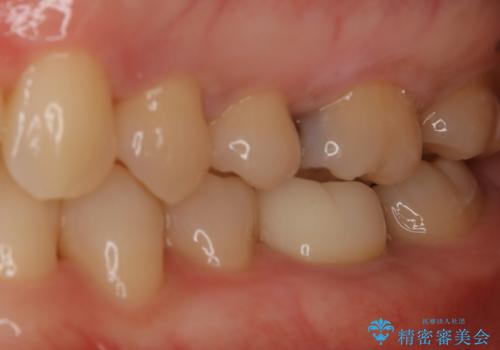

セラミックインレーは変色がなく耐摩耗性にも優れるため、長期的に良好な予後が見込める治療です。

セラミックインレー

歯の一部が虫歯になってしまった場合の治療法のひとつにインレーがあります。

虫歯になってしまった部分を含めて詰め物用に形を削り整え、型取りをし、出来上がってきた技工物をセメントで接着します。

自費治療では強度・色調・耐久性に優れたセラミックを使用した治療を選択する方が多いです。